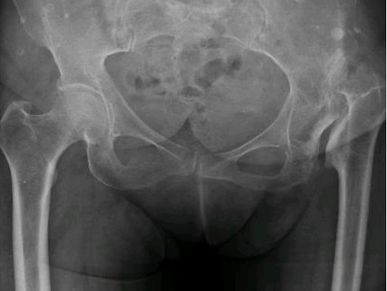

Planificación 3D displasia de cadera, implante de prótesis de cadera primaria en Rosario - Dr. Pablo Mariani Rovea